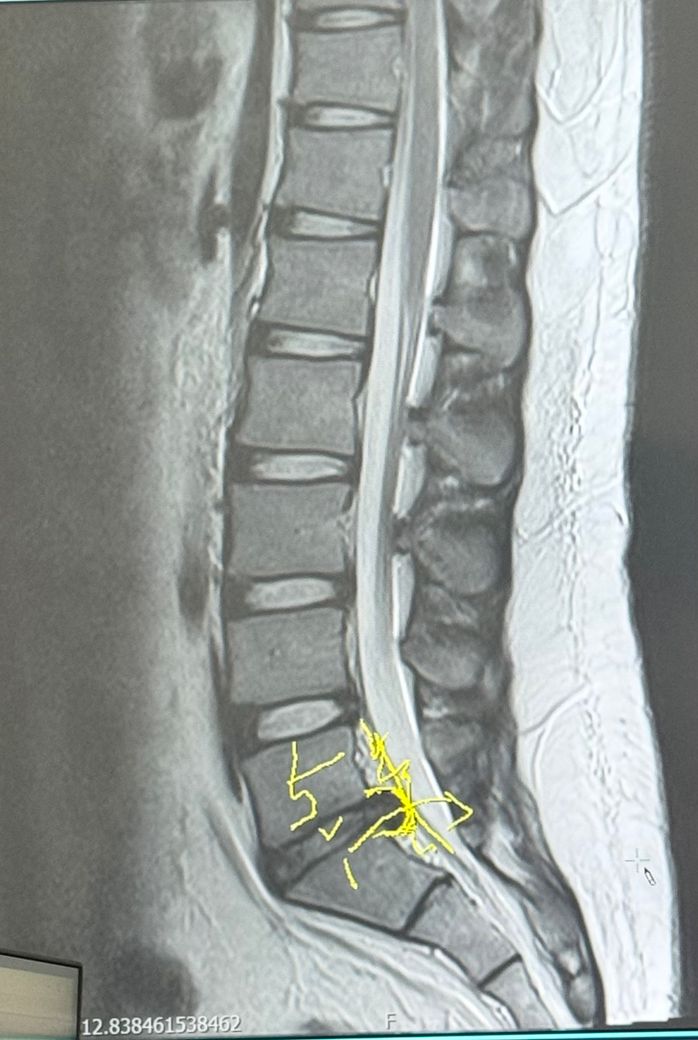

군복무를 두달 정도 남긴 상황에서 허리디스크 진단을 받았는데 아직 터지지는 않았습니다. 그런데 군복무 중에 터질 것 같은데 4급판정 기준을 통과하면 공익근무로 전환되나요?

• 1번 째 사진